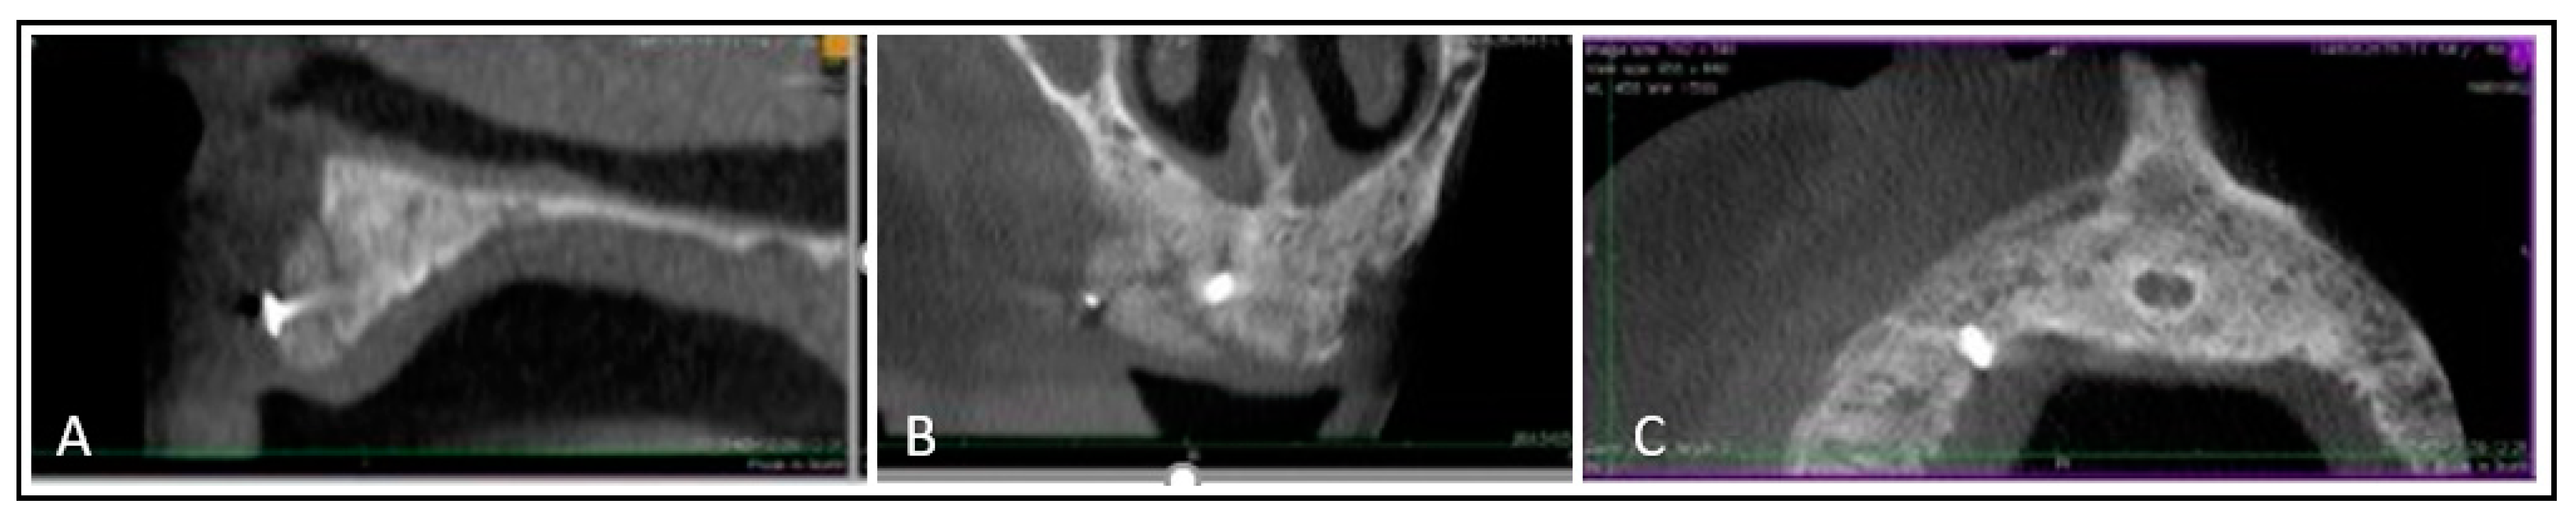

2. Case Report

2.2. Surgical Phase